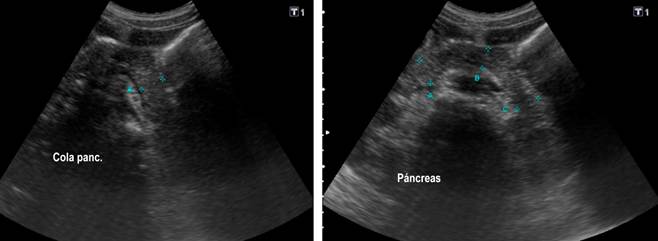

Se realizó una ecografía abdominal con hallazgos ecográficos de una vesícula con engrosamiento focal de sus paredes, asociado a líquido perivesicular, ascitis y páncreas con engrosamiento focal de la cola con un diámetro de hasta 22 mm (Figura 1). Laboratorios con elevación de aspartato-aminotransferasa (AST) 235 U/L y alanina-aminotransferasa (ALT) 93 U/L, amilasa sérica: 104 U/L, γ-glutamil transpeptidasa (GGT) 96 U/L, lipasa 813,4 U/L y proteína C-reactiva (PCR) 84,5 mg/dL, por lo cual se inició el manejo de pancreatitis aguda.

Fuente: historia clínica del paciente.

Figura 1 Ecografía de abdomen total. La imagen indica un engrosamiento focal de las paredes en la porción del cuerpo y cuello con líquido perivesicular. Páncreas con engrosamiento focal de la bolsa con un diámetro de hasta 22 mm.